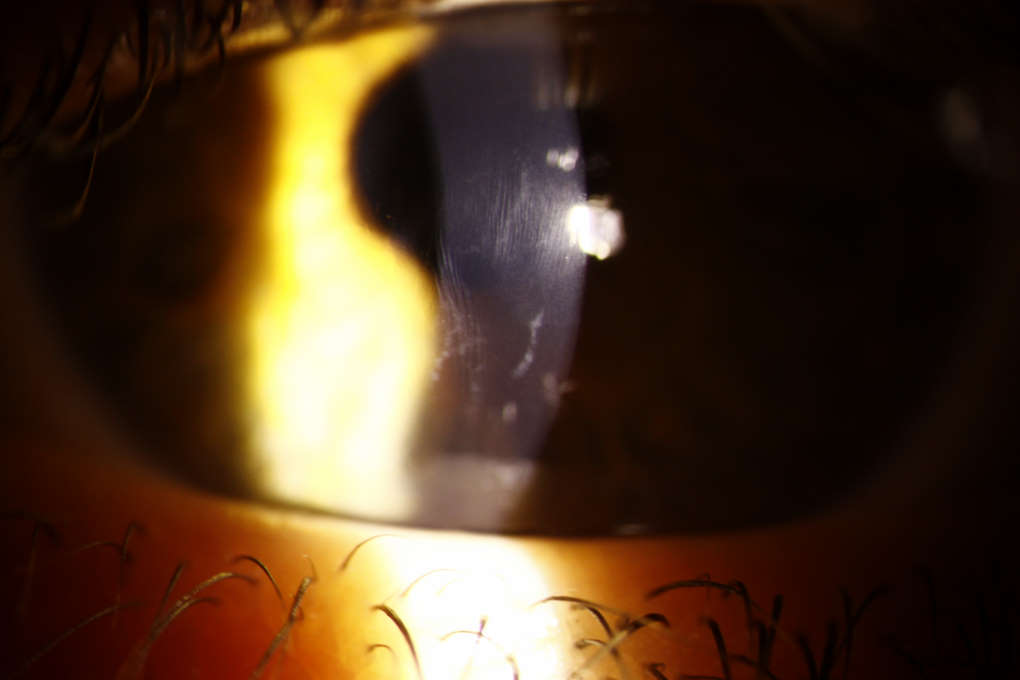

Vogt’s striae and anterior stromal scarring in an individual with DS and keratoconus

Prevalence estimates for keratoconus in DS range from 0.5-30%. The corneas of individuals with DS are inherently steeper, thinner and biomechanically weaker than non-DS counterparts. Given the clinical predisposition for keratoconus, it is conceivable that there may be a genetic link between keratoconus and chromosome 21. Others have attributed keratoconus in this group to mechanical trauma from eye rubbing, however, evidence for this is yet to be fully established.